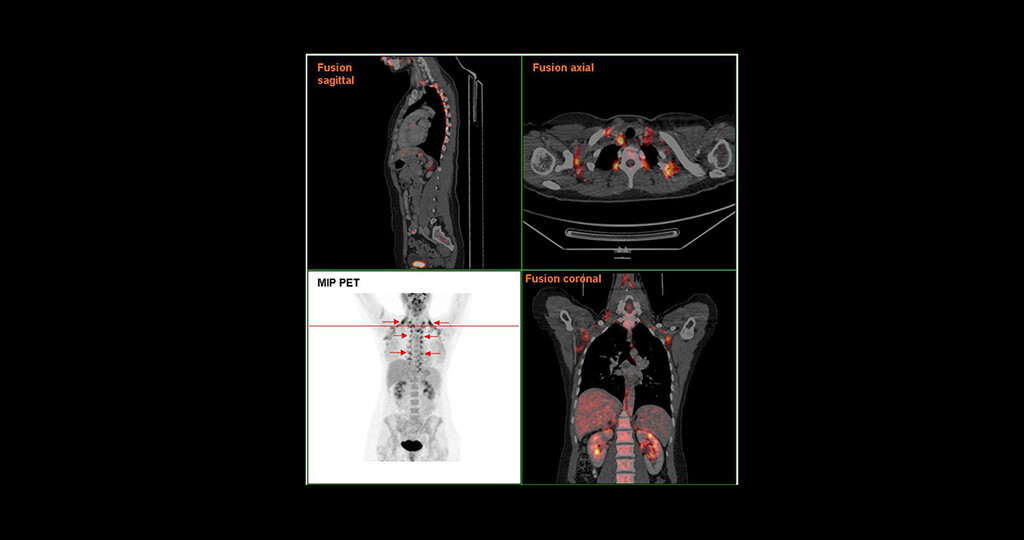

Für Erwachsene wurde angenommen, dass sie über keine aktiven braunen Fettzellen mehr verfügten. Im Jahr 2009 konnte in einer multinationalen Studie die Aktivität von braunem Fettgewebe bei Erwachsenen durch neue Methoden der funktionellen Bildgebung belegt werden. Hierzu wurde die klare Korrelation zwischen Aufnahme von Glucose in braunes Fettgewebe, gezeigt durch markierte Glucose in der Positronen-Emissions-Tomographie, und dem Body Mass Index dargestellt. Zwischenzeitlich ist klar, dass die Aktivität des braunen Fettgewebes bei Erwachsenen hoch variabel ist und von einer Vielzahl innerer und äußerer Einflüsse abhängt und mittels verschiedener Techniken nachgewiesen werden kann. Während das klassische weiße Fett sich besonders unterhalb der Haut und im Bereich des Bauchs findet, ist das braune Fettgewebe oberhalb der Schlüsselbeine (supraclaviculär) und neben den Wirbeln (paravertebral) der oberen Brust- und unteren Halswirbelsäule lokalisiert. Frauen scheinen einen höheren Anteil aktiven braunen Fettgewebes zu haben.

Das braune Fettgewebe kann einen relevanten Anteil am gesamten Energieumsatz haben. Mittels FDG-PET konnte bei gesunden Freiwilligen ein relevanter Glucose-Verbrauch nach Kälteexposition nachgewiesen werden. Die Aktivität des braunen Fettgewebes hängt von der Außentemperatur ab: Studien im Sommer zeigen weniger aktives Fettgewebe als im Winter, was auch zu unterschiedlichen Angaben der Häufigkeit von aktivem braunen Fettgewebe bei Erwachsenen führen kann. Neben der Wärmeproduktion greift das braune Fettgewebe positiv in den Glucose- und Fettmetabolismus ein. Das Ausmaß der physiologischen Rolle des braunen Fettgewebes bei Erwachsenen ist jedoch ungeklärt.